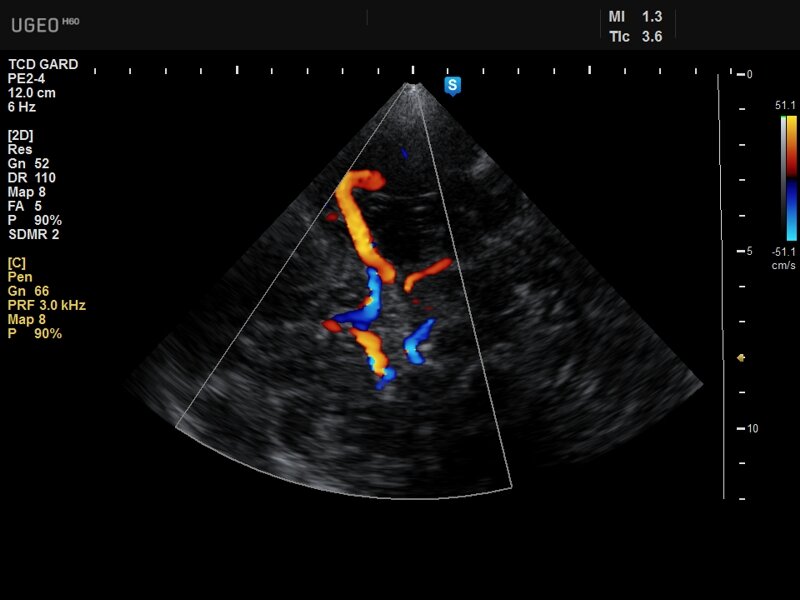

Транскраниальное Допплеровское исследование (ТКД) представляет собой уникальный неинвазивный метод оценки кровотока в сосудах головного мозга. Этот метод позволяет врачам исследовать церебральную гемодинамику, не прибегая к сложным и рискованным процедурам, что делает ТКД важным инструментом в неврологии и нейрохирургии.

ТКД основан на использовании ультразвуковых волн для измерения скорости кровотока в крупных артериях мозга. Ультразвуковые волны, отражаясь от движущихся кровяных клеток, изменяют свою частоту в зависимости от скорости кровотока. Это изменение частоты, известное как Допплеровский эффект, позволяет получить детальную информацию о скорости и направлении кровотока.

ТКД используется для диагностики и мониторинга ряда состояний, включая стенозы и окклюзии церебральных артерий, васоспазмы (особенно после субарахноидального кровоизлияния), и цереброваскулярные заболевания, такие как тромбозы и эмболии. Также метод активно применяется при оценке риска инсульта и для мониторинга пациентов во время и после хирургических вмешательств на сосудах головного мозга.